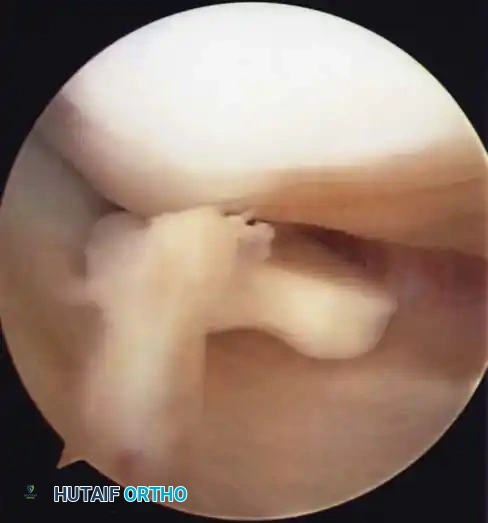

A critical factor in the failure of closed reduction is the interposition of soft tissue beneath the avulsed fragment. Kocher et al., in a review of 80 skeletally immature patients, identified entrapment of the anterior horn of the medial meniscus, the intermeniscal ligament, or the anterior horn of the lateral meniscus in:

* 26% of Type II fractures.

* 35% of Type III fractures.

Because of this high rate of soft-tissue interposition, forceful attempts to reduce Type III fractures by simply extending the knee are contraindicated, as this can further crush the entrapped meniscus.